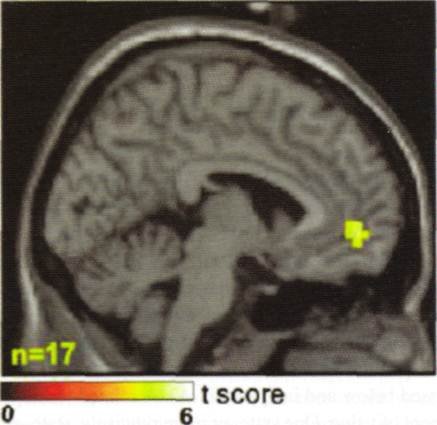

WYSIATI oznacza ogromny automatyzm. Potwierdzają to także badania, w których w trakcie prezentacji różnego typu bodźców równocześnie skanuje się aktywność różnych struktur mózgowych. Na zdjęciu zamieszczonym wraz z tym wpisem (przeskanowałem je z książki The Cambridge Handbook of Economic Behaviour –autorem rozdziału, z którego pochodzi są Terry Lorenz i P. Read Montague, natomiast autorem badania jest Samuel McClure i jego zespół) przedstawiony jest jeden ze skanów mózgu w pewnej grupie uczestników badania, których zadaniem było wybieranie „lepszego napoju” z pary coca-cola – pepsi. Badani studenci dokonywali swoich wyborów 15 razy, wiedzieli, że próbują colę i pepsi, ale nie widzieli, który napój próbują jako pierwszy, a który jako drugi (kolejność była oczywiście zmieniana). Wynik badania jest niesamowity! Natężenie sygnału w pokazanym na obrazku regionie mózgu było liniowo zależne od częstości wybierania coca – coli. Co więcej, osoby badane nie były w stanie odróżnić na poziomie większym niż przypadek obu napojów, gdy ich o to zapytano. Mózg jednak wiedział to za nich.